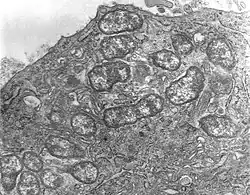

Scrub typhus or bush typhus is a form of typhus caused by the intracellular parasite Orientia tsutsugamushi, a Gram-negative α-proteobacterium of family Rickettsiaceae first isolated and identified in 1930 in Japan.[2][3]

Although the disease is similar in presentation to other forms of typhus, its pathogen is no longer included in genus Rickettsia with the typhus bacteria proper, but in Orientia. The disease is thus frequently classified separately from the other typhi.